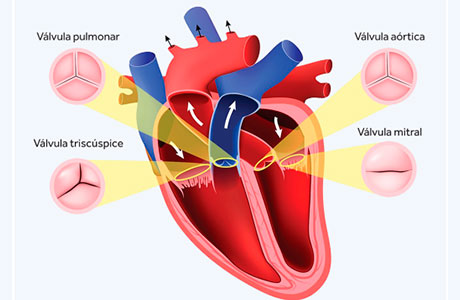

O que são ventrículos?

São as partes maiores e mais fortes do coração, as partes que bombeiam o sangue para a

circulação.

O ventrículo direito envia sangue para os pulmões.

O ventrículo esquerdo envia sangue para o restante do corpo.

O que é septo interventricular?

É uma estrutura que separa os ventrículos direito e esquerdo.

Como a cardiomiopatia hipertrófica atrapalha o funcionamento do coração?

De duas formas principais.

No jovem, pode causar instabilidade elétrica, responsável até eventos graves, inclusive em atletas.

Em pessoas com mais idade, pode causar cansaço, falta de ar, tonturas, “batedeiras” no coração – as palpitações, desmaio, dentre outros sintomas.

A presença de excesso de músculo na saída do coração atrapalha o envio do sangue para o restante do corpo.